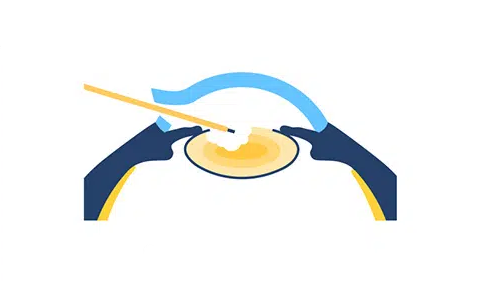

수정체낭 절개 및 백내장 제거

STEP 03

인공수정체 삽입